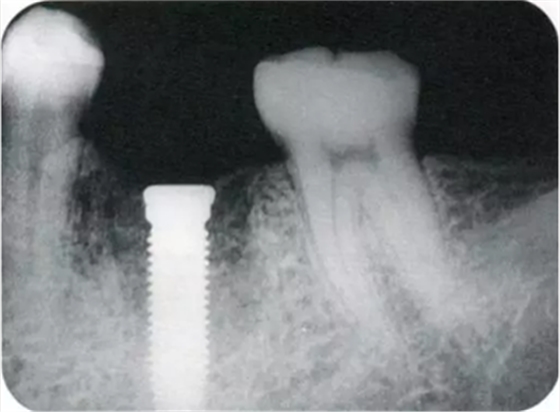

▲圖10-1,2

圖10-1 頰側(cè)和牙槽嵴有角化齦的存在,但是愈合期間內(nèi)覆蓋螺絲露出(Type3-Class2)